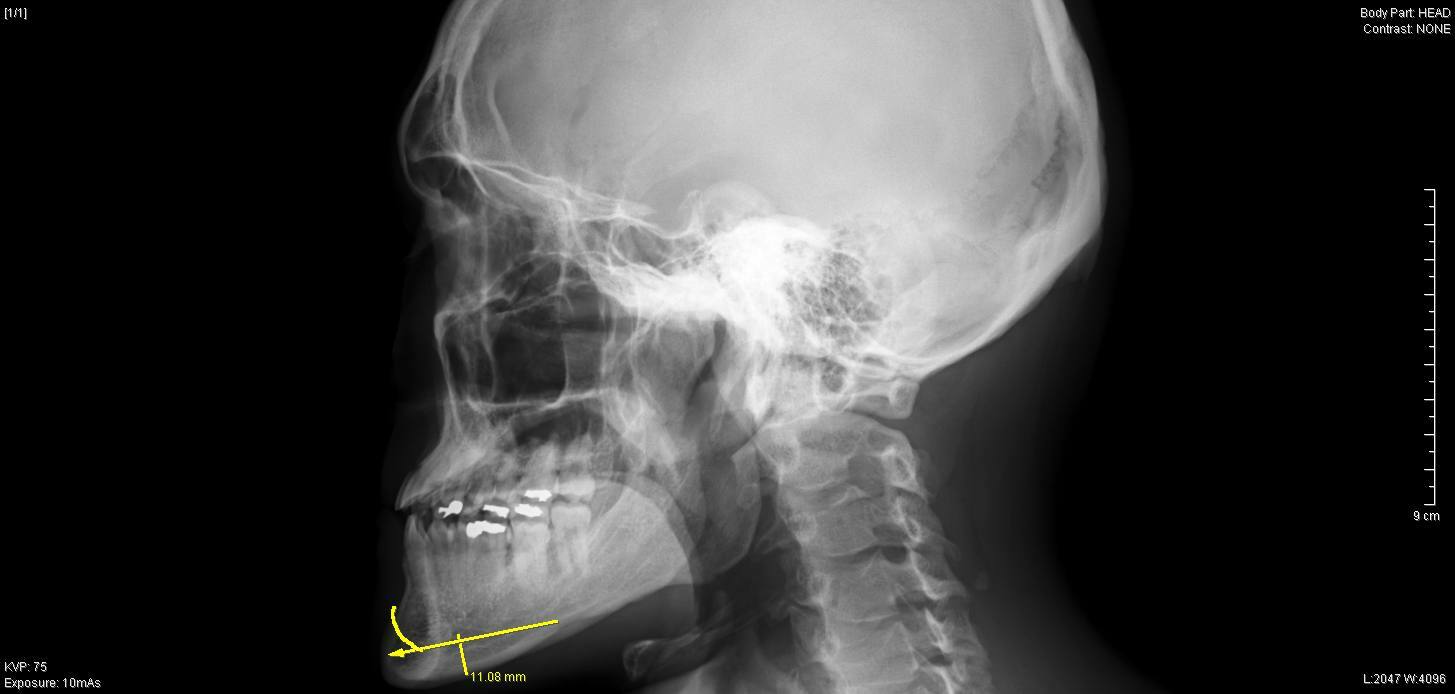

今回ご紹介する症例は、30代男性の顎の骨切り症例です。

過去に受け口改善目的のセットバック手術をされていましたが、

保険診療の適応でない下顎骨の骨切りはされていませんでした。

レントゲンでは、上下方向の切除幅は約1cm、

それに加えEラインを考慮して、

右側 最大 10mm

左側 最大 9mm

先端部 7mm